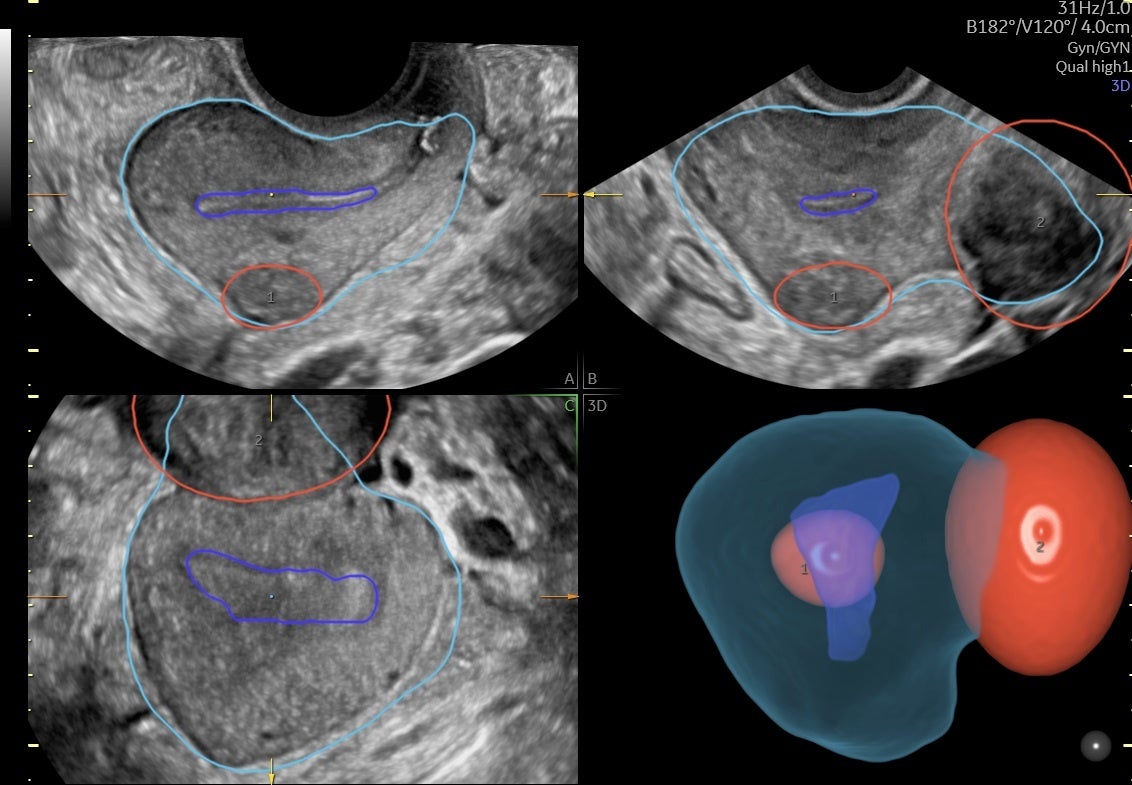

Volusonが長年培ってきた3D技術と、開発へのAI活用により、婦人科超音波検査の効率化に貢献する2つのアプリケーションを搭載しました。1つは、少ないステップで子宮筋腫の立体的位置関係を可視化する機能で、これまで断層像を用いて立体像をイメージしながら実施していた検査を3D画像化することで、簡便に子宮内膜との位置関係や、大きさを把握できるようサポートします。(画像➀)